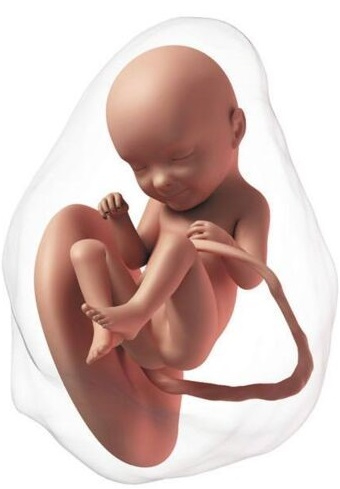

El proceso de la formación del embrión está ya prácticamente finalizado con una longitud de 30 mm. A partir de ahora empieza la etapa fetal, médicamente ya no es un embrión sino un feto. Ya ha completado la formación básica de todos los sistemas.

Ahora ya se mueve con frecuencia, pero son movimientos involuntarios; los músculos todavía tardarán en estar conectados con el cerebro. La cabeza es mucho más grande que el cuerpo, ya tiene orejas, nariz, hasta los párpados, los cuales estarán fusionados durante semanas. Los labios están formados y empieza a abrir la boca. Ya han aparecido pies y manos.

En esta etapa los genitales son exactamente iguales en niños y niñas. Tienen un tubérculo genital que más adelante se diferenciará en la forma de cada sexo. Su piel es translúcida, se puede ver el esqueleto a través de ella. En realidad, los huesos no tienen casi calcio, están formados por cartílago, pero la mayoría de los huesos ya tienen su forma definitiva.